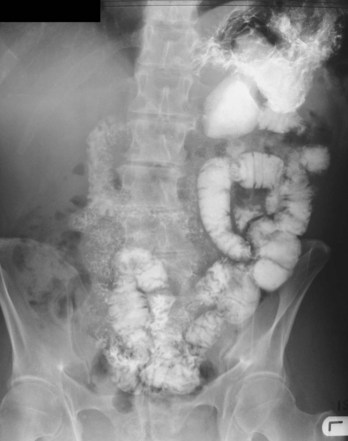

To demonstrate specific structures, such as bowel loops or arteries, it may be necessary to fill these structures with a substance that attenuates X-rays more than bowel loops or arteries do normally. It is, however, extremely important that these substances are nontoxic. Barium sulfate, an insoluble salt, is a nontoxic, relatively high-density agent that is extremely useful in the examination of the gastrointestinal tract. When barium sulfate suspension is ingested it attenuates X-rays and can therefore be used to demonstrate the bowel lumen (Fig. 1.4). It is common to add air to the barium sulfate suspension, by either ingesting “fizzy” granules or directly instilling air into the body cavity, as in a barium enema. This is known as a double-contrast (air/barium) study.

image

Fig. 1.4 Barium sulfate follow-through.

Gastrointestinal contrast examinations

High-density contrast medium is ingested to opacify the esophagus, stomach, small bowel, and large bowel. As described previously (pp. 7–8), the bowel is insufflated with air (or carbon dioxide) to provide a double-contrast study. In many countries, endoscopy has superseded upper gastrointestinal imaging, but the mainstay of imaging the large bowel is the double-contrast barium enema. Typically the patient needs to undergo bowel preparation, in which powerful cathartics are used to empty the bowel. At the time of the examination a small tube is placed into the rectum and a barium suspension is run into the large bowel. The patient undergoes a series of twists and turns so that the contrast passes through the entire large bowel. The contrast is emptied and air is passed through the same tube to insufflate the large bowel. A thin layer of barium coats the normal mucosa, allowing mucosal detail to be visualized (see Fig. 1.4).